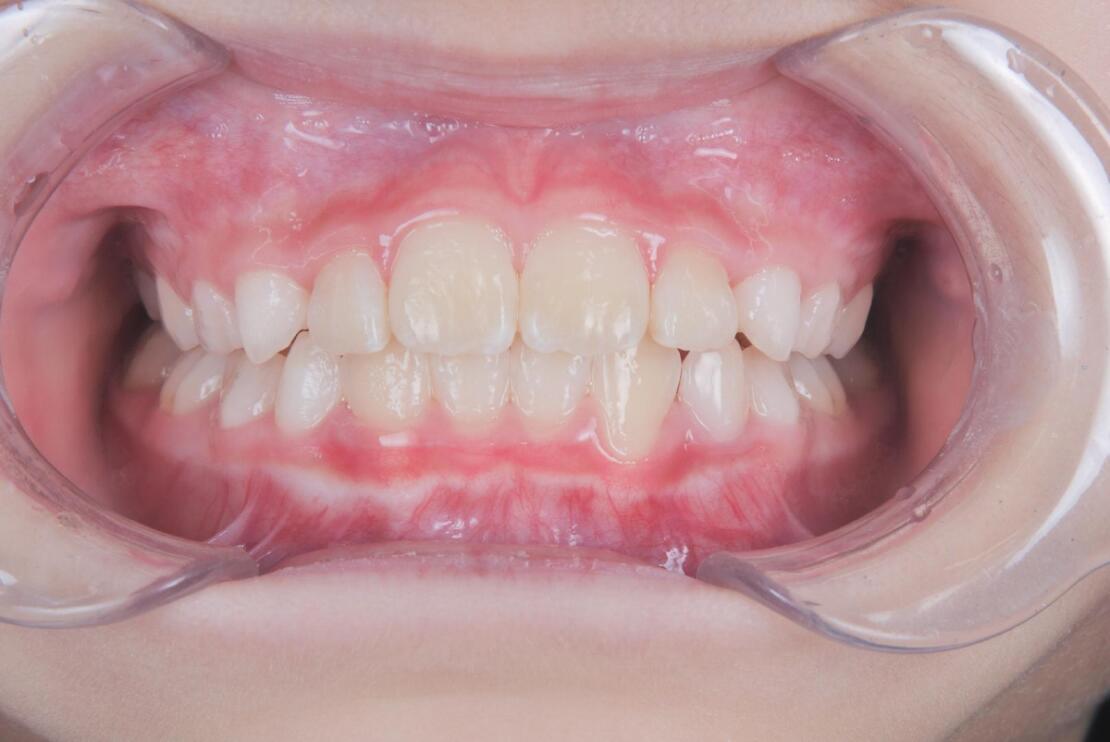

AFTER

治療は、マウスピース矯正インビザライン・ファーストにて矯正治療を行い、成長を活かしながら歯列と噛み合わせを整えていきました。治療期間は1年2ヶ月で、ガタつきと深い噛み合わせが改善し、将来を見据えた安定した歯列環境を整えることができました。

成長期だからこそ可能なアプローチで、早期に問題を改善できた症例です。